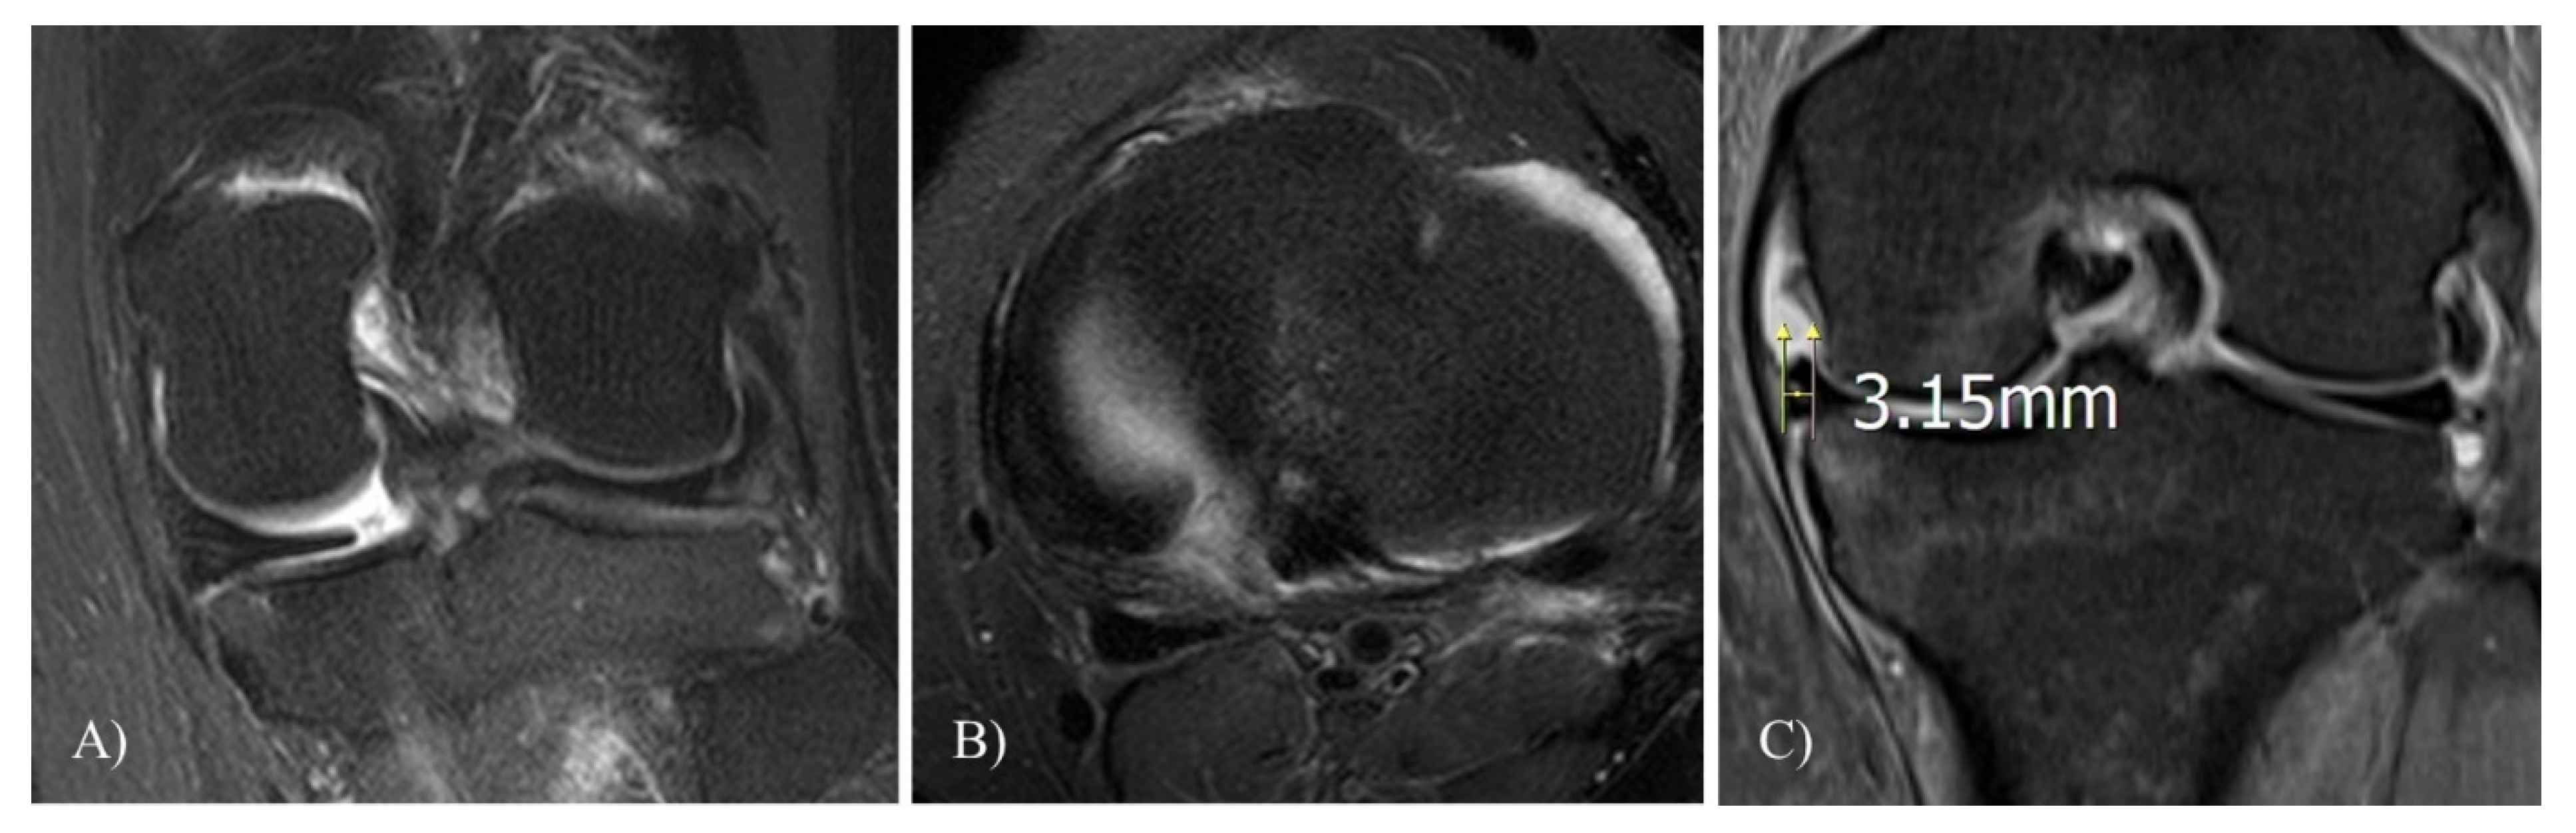

WBL

TVA

MOAKS

Meniscal Extrusion